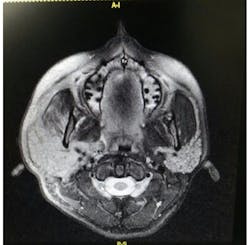

Sialdenosis is a non-neoplastic, noninflammatory swelling of the salivary gland in association with acinar hypertrophy and ductal atrophy. Sialdenosis results from systemic metabolic conditions similar to BN. Presentation is of nontender swellings that are often bilateral and symmetric7 (figures 3,4a,4b,5).

Parotid gland swelling occurs in patients suffering from BN. The exact cause of sialdenosis is unclear but the gland receives both sympathetic and parasympathetic innervation with BN and becomes dysregulated, causing hypertrophy. Whatever the cause, with the cessation of bingeing and purging, the parotid glands shrink back to their normal size, indicating a causal relationship.